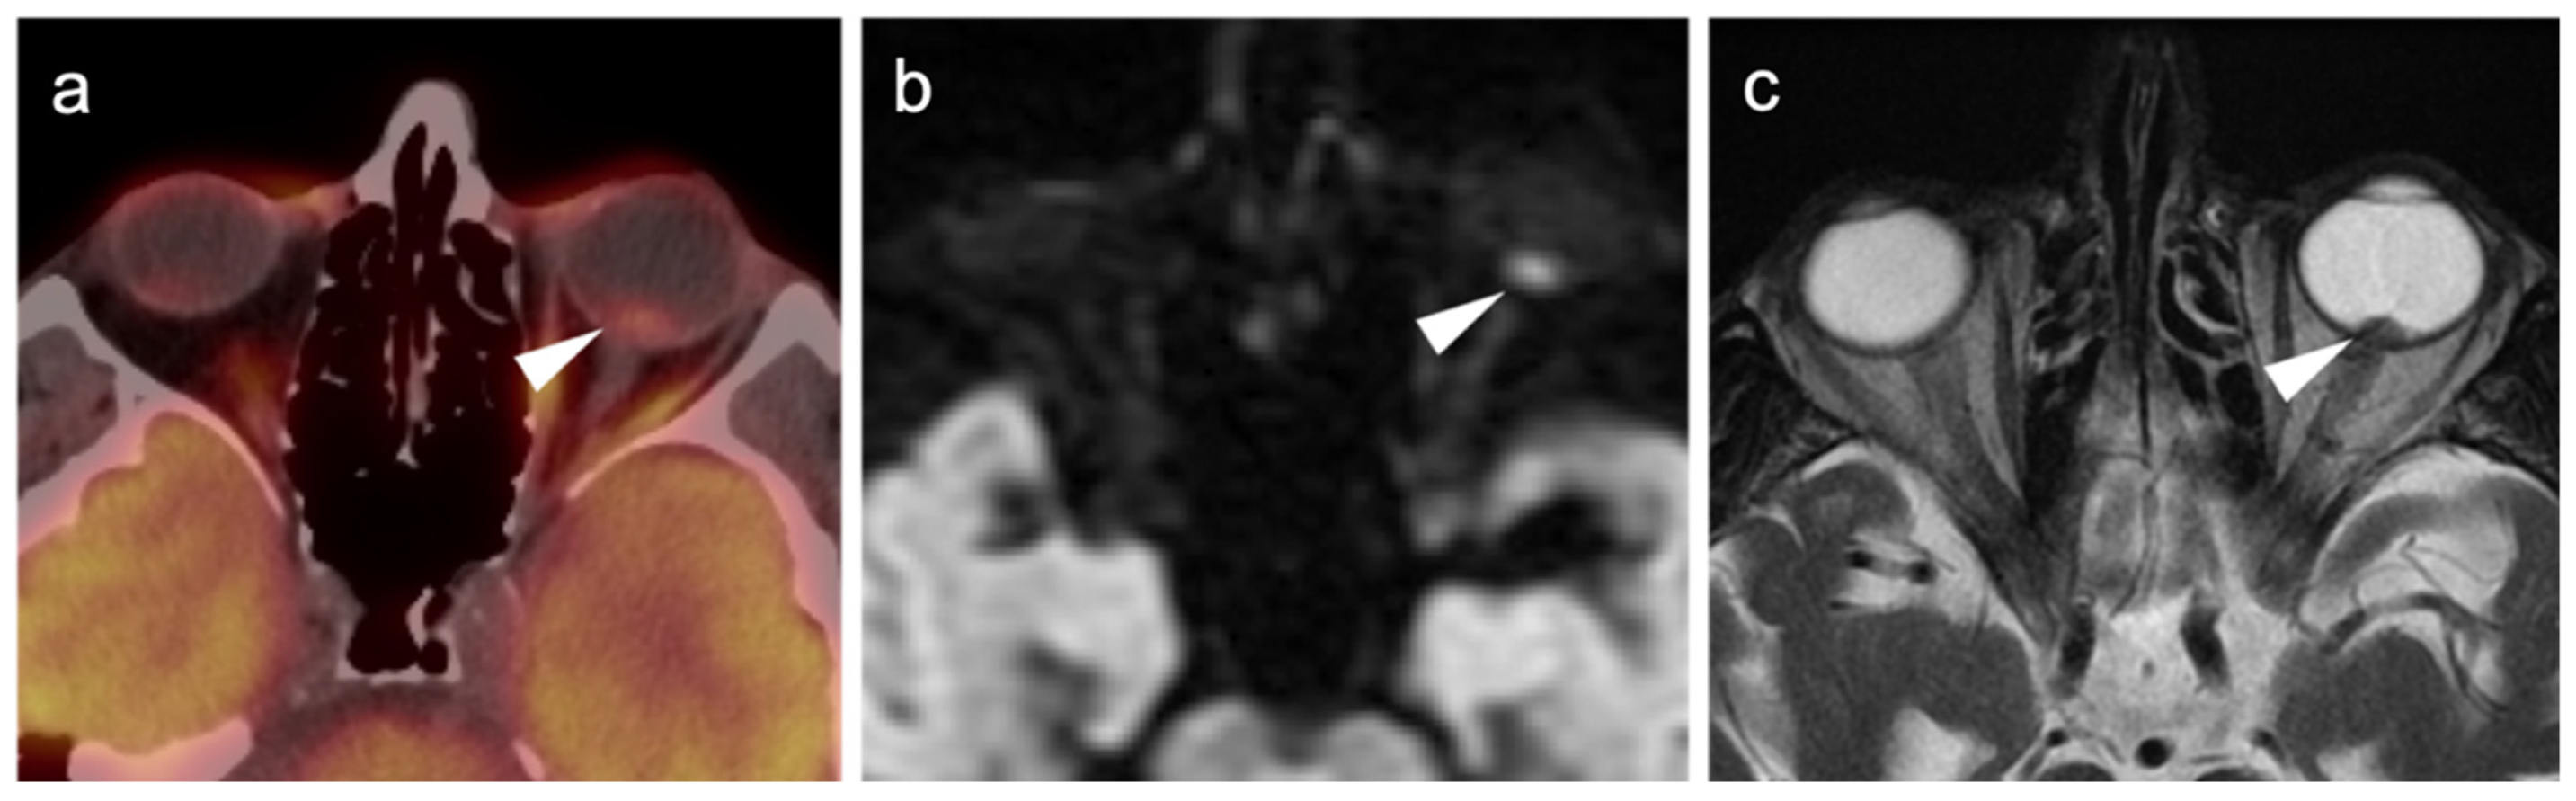

2.3.2. Ocular Melanoma

2.3.3. Mucosal Melanoma